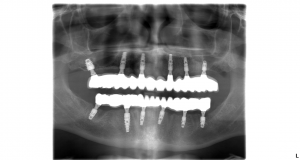

V prípade pána Tomáša bolo potrebných 6 zubných implantátov vo vrchnej a 6 zubných implantátov v spodnej čeľusti na ktoré sa nasadili 14 – členné keramické mostíky. U pni Márie bolo potrebných 7 zubných implantátov vo vrchnej čeľusti a 6 zubných implantátov v spodnej čeľusti.